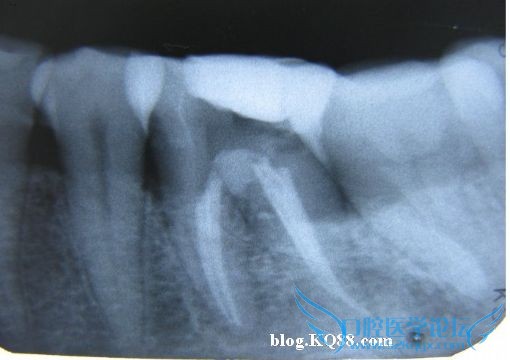

机括至25#06锥度,美松糊剂冷侧压充填

加压充填后烫断于根管口下2mm~4mm

近中偏位投照

正位投照,由于X光是平面成像,所以必须多角度投照确认,并且只能作为参考